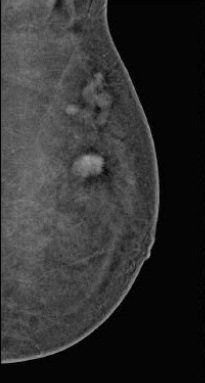

Diagnosi precoce di tumori invasivi con l'esame 3D Hologic1. Le slice di Tomosintesi rivelano un'area di distorsione architetturale, la cui natura tumorale sara' confermata dall'esame istologico, non visibile con la mammografia 2D.